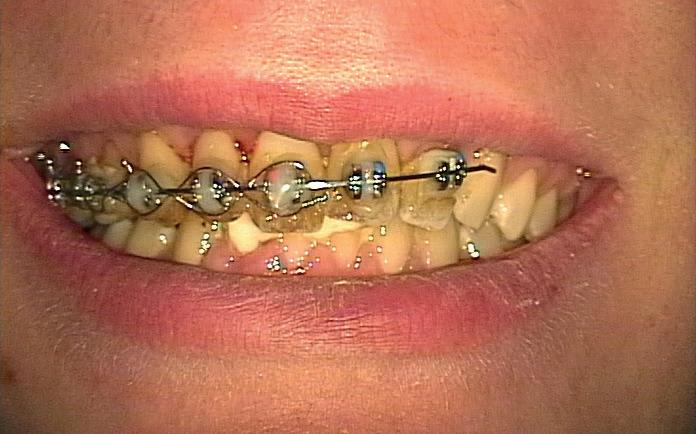

Onze verwijspraktijk EndoGooi in Bussum bestaat inmiddels 16 jaar. Hierdoor hebben we al veel patiënten voor langere tijd kunnen opvolgen. Zeker bij trauma is dat interessant én belangrijk, omdat het verloop van traumacasuïstiek zich lastiger laat voorspellen. In dit artikel bespreken wij een patiënt met verschillende soorten trauma.

Bij een 15-jarige gezonde jongen werd tijdens een caféruzie op zondagnacht een stoel tegen zijn gezicht gegooid. Hierbij was sprake van flink dentaal trauma:

• De 13 was geavulseerd.

• De 12 en de 11 waren naar palatinaal geluxeerd.

• In het onderfront waren kroonfracturen zichtbaar in de 42, 41 en 31.

Na de avulsie is de 13 bij de afdeling kaakchirurgie in een oplossing van fysiologisch zout bewaard (onbekend hoe lang na het trauma) en na ongeveer zes uur post-trauma onder anesthesie in de alveole teruggeplaatst. Toen zijn ook de 12 en de 11 gereponeerd en is er een staaldraadspalk aangebracht van de 14 naar de 22. Tevens is de lip gehecht. Er is niets aan de afgebroken ondertanden gedaan, maar dringend geadviseerd deze zo snel mogelijk te laten afdekken door de eigen tandarts.

Na zes weken zagen wij hem voor het eerst bij ons in de praktijk voor consult. Hij was klachtenvrij en kon redelijk kauwen met zijn tanden (afbeelding 1-6).